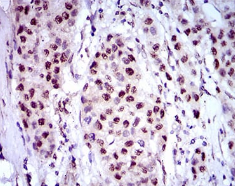

IHC    1/200 - 1/1000